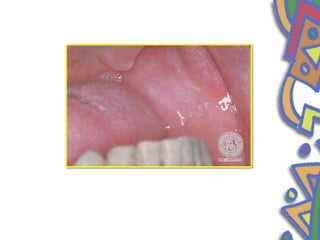

• Folliate papilla •Occurs as an area of vertical fold and grooves located on the extreme posterior lateral surface of tongue • Occasionaly mistaken for tumours or inflammatory disease • Bilaterally symmetrical

• 52.

• In somepeople the papilla are small and inconspicious whereas in others they are prominent